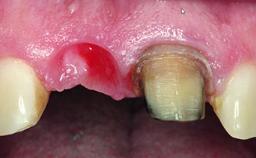

Replacement of a Perforated Upper Left Central Incisor: Early Placement of an RC Bone Level Implant

A 28-year-old patient presented at her general dentist’s office and complained about the appearance of her tooth 21. The patient had a history of trauma to this tooth. Endodontic treatment had been performed in the past and a crown placed on the tooth. A procedure to replace the old crown was performed by her dentist; however, a perforation on the middle third of the root occurred, and extraction of tooth 21 was suggested. Upon clinical and radiographic examination of the patient, who had been referred to us, replacement of tooth 21 by a dental implant appeared to be indicated.

Placement Protocol Early or late implant placement